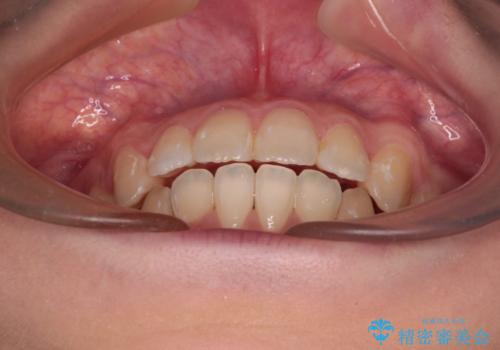

- 前歯のデコボコや口元の突出感、口の閉じにくさを気にして来院された患者様です。

上下左右第一小臼歯4本を抜歯し、ワイヤー装置にてデコボコを解消しながら口元を引っ込めるよう矯正治療を行うこととしました。

抜歯スペースを閉じている過程で、左側の上下犬歯が引っかかってしまい、進捗が停滞しましたが、当初予定の2年~2年半の間で無事に治療を終えることができました。